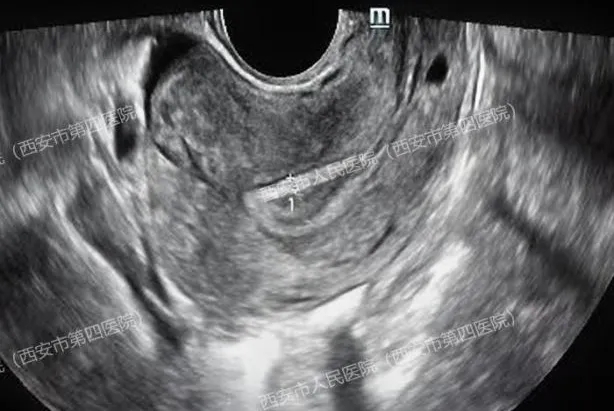

(上图腔内超声显示宫腔内未见孕囊,下图显示右侧卵巢小囊肿)